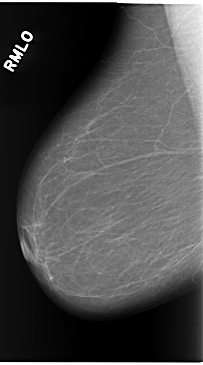

C_0119_1.RIGHT_MLO

RIGHT_CC LINES 5864 PIXELS_PER_LINE 3424 BITS_PER_PIXEL 12 RESOLUTION 50 NON_OVERLAY

RIGHT_MLO LINES 5840 PIXELS_PER_LINE 3248 BITS_PER_PIXEL 12 RESOLUTION 50 NON_OVERLAY